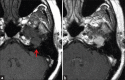

Schwannomas are benign soft-tissue tumors that arise from peripheral nerve sheaths throughout the body and are commonly encountered in patients with neurofibromatosis Type 2. The vast majority of schwannomas are benign, with rare cases of malignant transformation reported. In this pictorial review, we discuss the magnetic resonance imaging (MRI) appearance of schwannomas by demonstrating a collection of tumors from different parts of the body that exhibit similar MRI characteristics. We review strategies to distinguish schwannomas from malignant soft-tissue tumors while exploring the anatomic and histologic origins of these tumors to discuss how this correlates with their imaging findings. Familiarity with the MRI appearance of schwannomas can help aid in the differential diagnosis of soft-tissue masses, especially in unexpected locations.